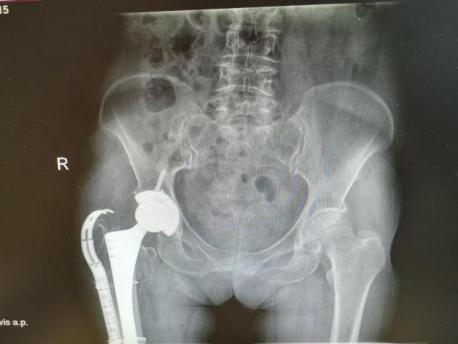

为提升区域内基层医疗机构糖尿病足诊疗服务能力、促进青年医师对糖尿病足的规范化诊治水平,遵义市第二城市医疗集团总院(贵州航天医院)圆满举办贵州省继续医学教育项目——胫骨横向骨搬移技术治疗糖尿病足专题研讨班。 贵州航天医院党委委员、副院长彭亮出席会议并致辞,遵义市第二城市医疗集团各成员单位,以及红花岗区、汇川区、绥阳县、桐梓县等多个区县的基层医疗机构骨干医师参加会议。 研讨班 本次研讨班以胫骨横向骨搬移技术在糖尿病足治疗中的应用为核心主题,围绕糖尿病药物治疗与生活方式管理策略、围手术期血糖精准调控要点、胫骨横向骨搬移技术典型病例深度解析、糖尿病足的临床分型与个体化治疗方案制定等临床实践中的热点与难点展开深入探讨,通过专题授课、案例研讨、互动交流等多元化形式,为参会者搭建了理论与实践结合的学习平台。 此次研讨班不仅为区域内基层医院搭建了学术交流与经验共享的平台,更对推动糖尿病足预防、诊断与治疗的规范化、系统化发展起到了积极作用,有效助力青年医师更新专业知识体系、提升临床技能,为进一步保障区域内糖尿病足患者的健康奠定了坚实基础。 贵州航天医院骨科专家简介 陈明勇 骨一科主任,副主任医师 临床擅长:从事创伤骨科工作约20年,对骨缺损、骨不连、骨肿瘤、肢体畸形等的肢体矫形重建及功能重建,慢性化脓性骨髓炎的根治治疗、糖尿病足的保肢治疗、快速康复理念(ERAS)下的老年骨折的诊治,四肢复杂骨折的诊治,四肢骨折等微创手术治疗具有丰富的临床经验。 2004年毕业于遵义医学院临床专业,曾在中国人民解放军总医院、广西医科大学第一附属医院、上海第六人民医院骨科进修。中国中西医结合学会骨伤科专业委员会横向骨搬移治疗糖尿病足及微血管网再生学组首届委员,遵义市医学会创伤分会常务委员。 瞿 晖 骨科党支部书记,骨二科主任,副主任医师 临床擅长:对骨科的常见病、关节外科、脊柱外科及运动医学疾病的诊治具有丰富的临床经验,熟练掌握骨科手术操作技术。 毕业于遵义医学院临床医学系,2005年前往广州中山大学第一附院骨显微医学部进修学习,2011年前往成都华西医院进修学习,并多次在省内外学习骨科相关知识,是中华医学会骨科分会会员。 赵小锋 中共党员,骨二科副主任,副主任医师 临床擅长:从事骨科临床工作11年,对骨科常见病、多发病诊疗有较为丰富的临床经验,擅长脊柱相关疾病诊断及治疗,尤其是颈、腰、腿疼痛疾病诊断及治疗,擅长胸腰椎骨折微创经皮穿刺内固定术、经皮穿刺椎体成形术、经皮穿刺脊柱内镜下腰椎间盘摘除术、单纯开创腰椎间盘摘除术、腰椎滑脱复位椎间植骨椎融合内固定术、腰椎管狭窄减压融合内固定术及人工髋、膝关节置换术等。 2012年毕业于遵义医学院外科学专业硕士研究生,2019年参加“遵义市115医学人才精英计划”于上海交通大学第一附属医院培训学习,2023年于北京大学第三人民医院脊柱外科进修学习,曾获得遵义市优秀医师荣誉称号。 遵义市手外科第一届委员,遵义市医学会创伤分会第一届委员,遵义市医学会创伤分会第二届委员,贵州省康复医学会第三届脊柱脊髓专业会委员,遵义市医学会烧伤与整形外科学分会委员,发表论文5篇,其中国家级核心期刊1篇,SCI论文1篇,主持市级课题1项并结题,参与市级课题2项。 赵兴东 骨科主任医师 临床擅长:擅长骨科的常见病及各种创伤、四肢骨折创伤修复、骨感染、手足疾病的诊治和手足体表畸形的矫形整复,熟练掌握骨科四肢骨病及创伤的手术操作技术,尤其在四肢关节复杂性损伤、手足外伤、组织缺损创面、难治创面的皮瓣修复方面及平足、高弓足矫形方面及四肢慢性疼痛诊治、康复方面具有丰富的临床经验。 硕士研究生,毕业于遵义医学院临床外科系,2015年前往山东省立医院手足外科进修学习;遵义市医学分会创伤分会第一、二届委员,遵义市手外科医学会第二委届员会常务委员;在省级及省级以上期刊发表文章9篇,参编著作2部,参与主持并完成市级课题1项,参与市级课题2项、省级课题1项。 张艳金 中共党员,骨科副主任医师 临床擅长:从事骨外科工作16年,对复合伤、多发伤的救治、四肢骨干骨折、关节周围骨折、骨肿瘤、骨髓炎等诊治具有丰富的临床经验。 中共党员,硕士研究生,2006年本科毕业于山西医科大学第二临床医学院,2011年研究生毕业于北京军区总医院;在“老年COPD患者合并髋部骨折的诊治”国际合作课题组研究两年,在老年髋部骨折的诊治方面具有丰富的经验,并发表论文6篇;主持遵义市级课题1项,承担遵义医科大学的临床教学工作,获得遵义医科大学优秀带教老师荣誉。编撰有《骨科疾病诊疗精粹》一书,开展2项新技术,编撰地方规范《务川自治县创伤骨科常见疾病诊疗规范》一书。 张俊凯 骨科副主任医师 临床擅长:从事骨科临床工作28年,对创伤骨折、骨感染、骨缺损、骨不连等外科诊治,四肢骨折的微创手术治疗,四肢复杂骨折(如关节内粉碎性骨折、多发骨折等)的损伤控制及手术治疗等具有丰富的临床经验。 1995年毕业于遵义医学院临床专业,2009年前往复旦大学附属医院骨科进修1年。 卢懿明 中共党员,骨科副主任医师 临床擅长:从事骨科工作18年,对创伤骨折、四肢骨折的微创手术治疗、四肢复杂骨折(如关节内粉碎性骨折、多发骨折等)的损伤控制及手术治疗,尤其是髋部骨折的PFNA等微创技术,踝关节骨折、膝关节周围骨折的Mipo微创技术等具有丰富的临床经验,开展了4项新技术,发明6项新型专利技术。 2005年毕业于遵义医学院临床专业,2017年,前往南方医科大学第三附属医院骨科进修半年,回院后运用Mipo技术对骨干骨折及干骺端骨折的治疗技术,同时积极开展骨盆骨折、髋臼骨折腹直肌外侧切口的应用;发表了多篇专业论文,经常参与省内外学术交流会授课,获得医院荣誉称号多个。 邬夏荣 骨科副主任医师 临床擅长:从事骨科工作16年,对四肢复杂骨折、骨肿瘤的诊治,尤其是足踝创伤、慢性踝关节损伤、平足症等诊疗具有丰富的临床经验。 2006年毕业于遵义医科大学临床医学专业,曾在陆军军医大学西南医院进修学习,发表多篇骨科学术论文。 余德怀 中共党员,骨科副主任医师 临床擅长:从事骨科工作10余年,对运动医学、骨关节、脊柱外科常见病、多发病的诊治具有丰富的临床经验。 硕士研究生,2011年毕业于遵义医学院临床医学专业,曾前往遵义医科大学附属医院运动医学专业进修学习;是贵州省医学会运动医学分会青年委员,西部关节镜联盟委员;发表多篇骨科学术论文。 冯 乾 骨科副主任医师 临床擅长:从事骨科工作近20年,熟练掌握骨科多发病及常见病的诊治,尤其对脊柱退变性疾病的诊断及治疗具有丰富的临床经验,主要研究脊柱微创相关治疗方式,能熟练开展椎间孔镜及UBE。 曾前往北京大学第三医院进修学习疼痛及椎间孔镜、首都医科大学友谊医院专业进修脊柱内镜;是贵州省康复医学会第三届脊柱脊髓专业委员会委员;发明专利3项、发表脊柱外科专业论文多篇。 贵州航天医院骨科简介 基本情况 贵州航天医院(原3417医院)骨科组建于1968年,前身是以创伤和断肢(断指)再植闻名于世的上海市第六人民医院骨科,中国断肢(断指)再植的奠基者、中科院院士陈仲伟等专家莅临科室指导医疗和教学,并在70年代开展了贵州省首例断肢(断指)再植手术。组建50余年来,诊治患者已逾百万,挽救了无数的伤病员,成为了保障遵义地区人民群众健康的重要支撑。 经过几代人的不懈努力,今天的骨科,已由创伤骨科发展至骨病、骨肿瘤、骨结核等领域,现有脊柱外科、关节外科、四肢创伤、手足外科四个亚专科,成为了集医疗、教学、科研于一体的综合学科,是贵州省临床重点专科、遵义市临床重点专科、遵义市骨科临床医学中心、遵义市基层骨科专科联盟理事长单位。 科室目前开放床位110张,共有医护人员50余人,副高级以上专家18人,硕士研究生15人。拥有一流骨科医疗设备多台,每年不定期选派优秀技术骨干到全国各大知名医学院校进修、学习、参观、交流,并邀请国内、国外知名专家教授来院进行交流、指导,通过不断引进国内外先进的诊疗技术,科室医疗技术水平稳步提升,为广大人民群众提供了优质的医疗服务。 专科特色 骨一科 (一)骨缺损、骨不连的肢体与功能重建 胫骨横向骨搬移技术治疗糖尿病足: (二)慢性骨髓炎的根治治疗 (三)肢体缺血性疾病如糖尿病足、脉管炎的保肢治疗 (四)皮瓣修复 (五)复杂创伤的治疗 (六)老年髋部骨折及小儿骨折快速手术 老年髋部骨折: 骨二科 (一)胸腰椎骨折微创经皮椎弓根螺钉固定术 (二)老年性骨质疏松性患者腰椎滑脱脊柱内固定术(骨水泥螺钉) (三)V形双通道脊柱内镜技术(VBE)腰椎融合术治疗腰椎退行性疾病 (四)老年性骨质疏松性骨折(PVP/PKP)术 (五)人工髋关节置换术 (六)双侧股骨头坏死人工全髋关节置换 (七)右侧全髋置换术后假体周围骨折翻修 (八)人工膝关节置换术 (九)人工膝关节假体松动翻修 (十)关节镜技术 传统手术切口 关节镜技术切口 诊疗范围 骨一科 1.四肢创伤、矫形。 2.手、足踝外科。 骨二科 End